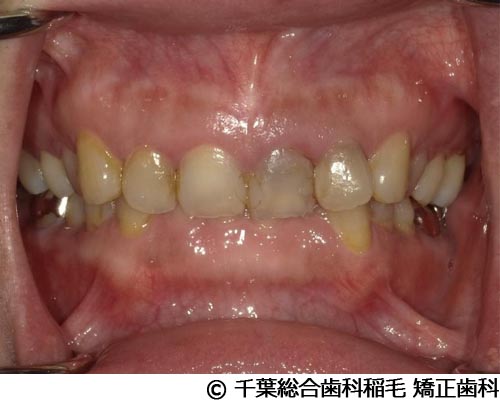

【症例4】上顎前歯1本インプラント埋入手術

- 治療前

- 治療後

- 治療名

- 上顎前歯1本インプラント埋入手術

- 費用

- 600,000円(税込)

- 期間

- 11ヵ月

治療内容

患者様の症状

前歯の色味が気になりご来院されました。

治療法

根っこが割れていたため抜歯となりました。

インプラント、ブリッジ、義歯それぞれのメリット、デメリットをお話させていただき、インプラントでの治療を選択されました。 -

治療結果

機能性、審美性ともに改善し、満足していただけました。

現在も定期検診で拝見させていただいています。